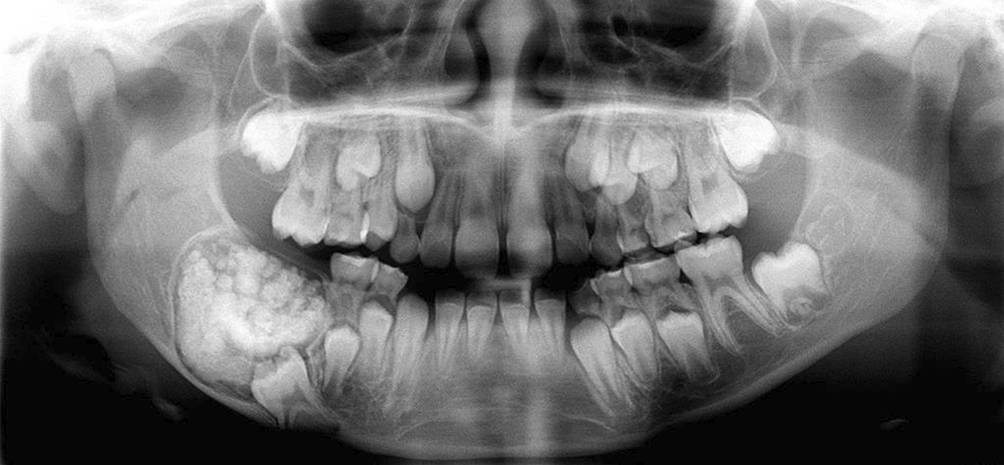

Ein subjektiv beschwerdefreies 8‑jähriges Mädchen stellte sich auf Überweisung durch den ambulanten Zahnarzt aufgrund eines verzögerten Zahndurchbruchs im Unterkieferseitenzahnbereich rechts in der Poliklinik für Kieferorthopädie unseres Zentrums vor. Inspektorisch ohne sichtbare Mukosaveränderung war eine nicht druckdolente Vorwölbung im Vestibulum Regio 46/47 tastbar. Daraufhin wurde ein Orthopantomogramm (OPG; Abb. 1) angefertigt.

Abb. 1

OPG. Regio 46–48 scharf begrenzte strahlendichte Raumforderung, die der Zahnhartsubstanz entspricht, mit feinem peripherem Aufhellungssaum und zarter Randsklerose. Zahnanlagen von 47 und 48 nicht erkennbar